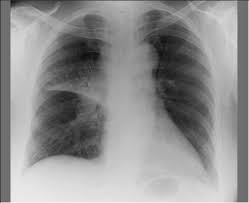

Does tuberculosis linger and then jolt you like a dodgy appliance, waiting to strike? My lungs are probably decrepit from the pollution from my stay in China, but I hopefully did not contract this ------->

However after further research, I found that one in three people in the world are thought to have TB! In 2007 there were an estimated 13.7 million chronic active cases, 9.3 million new cases, and 1.8 million deaths, mostly in developing countries. The distribution of tuberculosis is not uniform across the globe; about 80% of the population in many Asian and African countries test positive in tuberculin tests, while only 5–10% of the US population test positive.